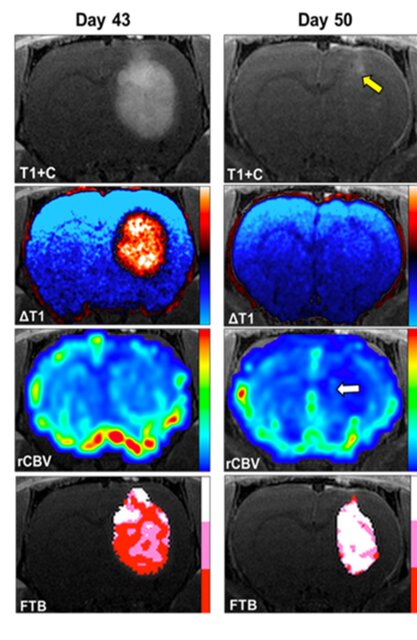

نتایج تحقیقات پیش بالینی نشان می‌دهد که ترکیب آهن مانند برای درمان بیماران مبتلا به گلیوبلاستوما، یک سرطان تهاجمی مغز، نویدبخش است.